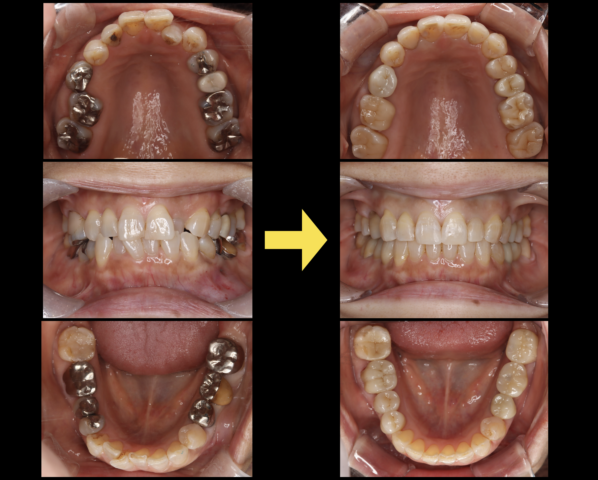

術前・術後 比較

綺麗な歯列が獲得でき、審美的・機能的な状態となった